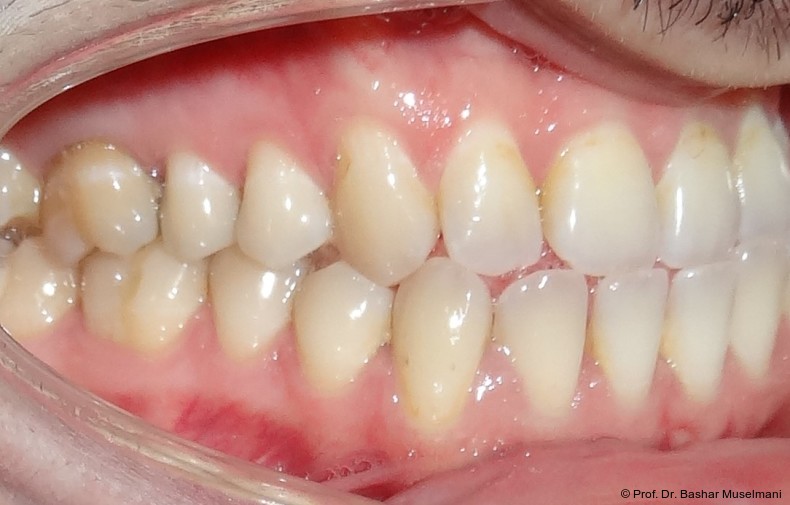

Der Patient (28 Jahre 8 Monate) stellte sich mit einer skelettalen Klasse III sowie einer Mittellinienabweichung nach links vor.

Klinische Befunde

• leicht konkaves Gesichts- und Mundprofil

• posterior positionierter Unterkiefer (VW)

• retroinkliniert stehende Unterkieferfront

Die Abbildungen 1 bis 3 zeigen die initiale klinische und radiologische Ausgangssituation.